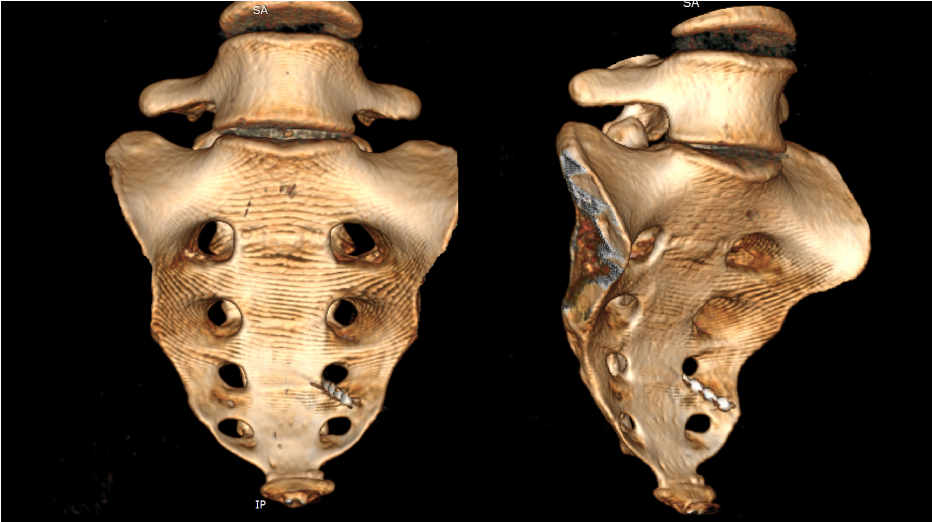

Пациенткам обеих групп проводилась имплантация электродов для стимуляции крестцовых корешков через отверстие S3 с одной или двух сторон (рис.1,2), или в крестцовый канал трансхиатально или ретроградно в зависимости от анатомии крестца и клинической картины. На выбор стороны стимуляции влияли такие факторы как степень развития крестцовых отверстий, желание и образ жизни пациента, визуализируемость отверстия S3 на рентгене. Значимой разницы в эффективности стимуляции в зависимости от стороны стимуляции нами выявлено не было. Необходимо отметить, что двустороннюю стимуляцию мы применяли только в 2 случаях, когда недержанию сопутствовала двустороння тазовая боль. В случае боли с одной стороны, электрод устанавливали с той же стороны, при отсутствии боли, у женщин только АИ сторона определялась вышеназванными факторами.

Рис. 1. 3D-реконструкция КТ крестца и копчика пациентки с имплантированным электродом для нейростимуляции S3 корешка слева по поводу послеродовой АИ.